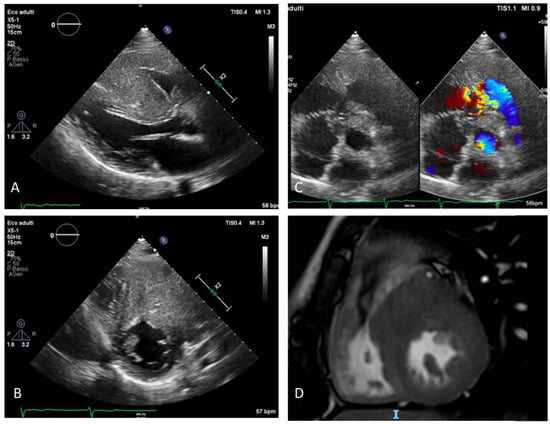

2. Case Description